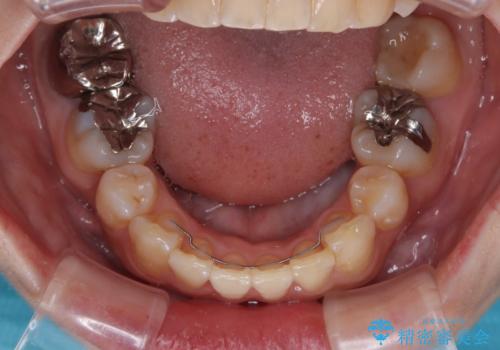

第二小臼歯抜歯としたため、治療期間は長くなりましたが、満足のいく仕上がりとなりました。